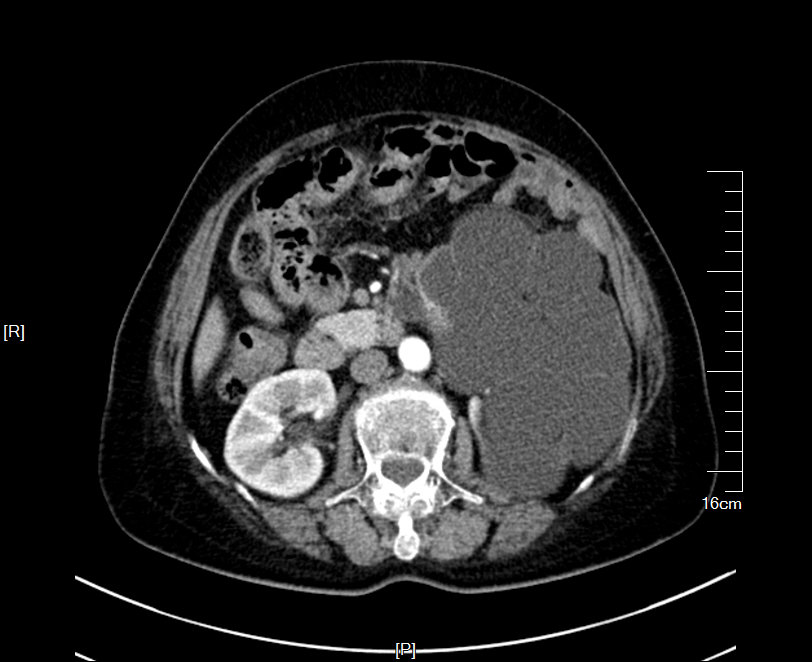

2016年04月手术患者,女性,32岁,昆山人,五年前曾因右输尿管结石引起肾绞痛于当地消炎补液解痉排石处理,疼痛缓解后未于重视,其间从未予复查,2周前出现右腰痛,与当地诊所就诊后予以震波碎石无效,并出现发热,急诊来我院就诊,CT:右肾萎缩,右侧肾脏积水,右侧输尿管多发结石形成石街约4.5*1.5cm,GFR:右侧17.2ml/min,左侧43.2ml/min。因左侧健肾代偿,肾功能正常:Cr 132umol/L;术前诊断:右输尿管下段多发结石 右肾萎缩 肾功能不全,鉴于右输尿管结石梗阻时间太长,肾功能不全,已处于失代偿期,最终也只能行右侧输尿管下段切开取术,解除输尿管下段梗阻,尽可能保护已经萎缩的肾脏,该患者预后不良。

增强CT检查提示:右侧肾脏积水,右肾萎缩,右输尿管下段多发结石